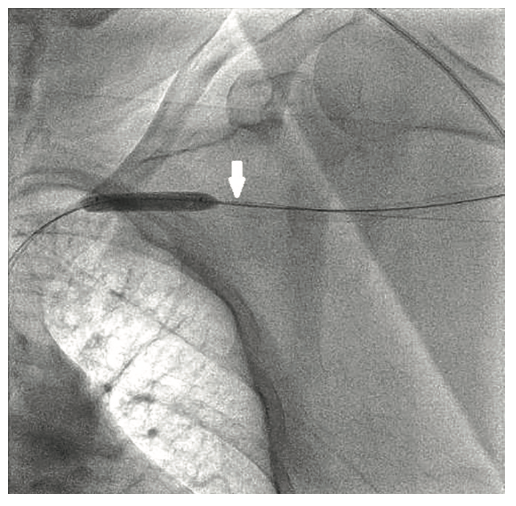

The right groin was accessed using fluoroscopic guidance. A micropuncture sheath was placed and upsized to a 7 French, 45 cm Destination sheath (Terumo) in the right groin. We accessed the right radial, but could not get good flow. Therefore, we ended up using the ulnar artery with ultrasound guidance and placed a Terumo 5/6 Slender sheath in the ulnar artery. We proceeded to access the left axillary artery. We placed a Judkins right (JR)4 catheter in the left subclavian and did a selective angiogram, documenting the location of the thoracoacromial artery and circumflex humeral (Figure 4); then using a Chiba biopsy needle (Cook), accessed the axillary artery and placed a 5-French 30 cm sheath (Cook)(Figure 5). We used the 15 cm biopsy needle to allow us a shallow angle of approach with the patient’s body habitus and to avoid “kinking” the sheath. We then switched out for the Lunderquist wire (Cook Medical), placed an 8 Fr sheath, and performed a pre-close using two Perclose devices (Abbott Vascular) (Figure 6).